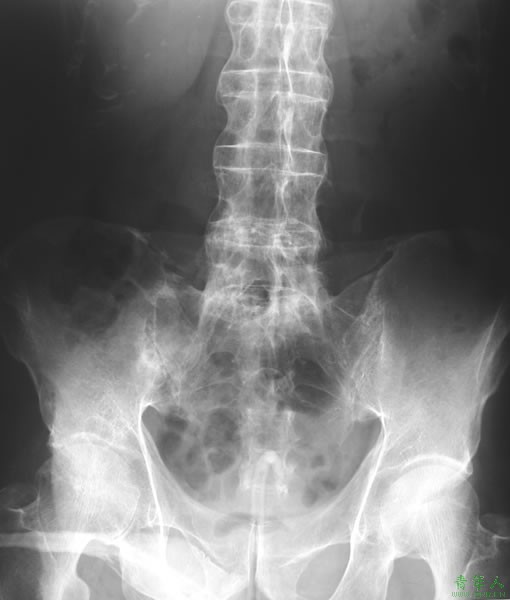

(2)X线:骶髂关节软骨下骨缘模糊,骨质糜烂,关节间隙模糊,骨密度增高及关节融合。通常按X线片骶髂关节炎的病变程度分为5级:0级为正常;Ⅰ级可疑;Ⅱ级有轻度骶髂关节炎;Ⅲ级有中度骶髂关节炎;Ⅳ级为关节融合膝关节病。脊柱的X线表现有椎体骨质疏松和方形变,椎小关节模糊,椎旁韧带钙化以及骨桥形成。晚期广泛而严重的骨化性骨桥表现称为“竹节样脊柱”。耻骨联合、坐骨结节和肌腱附着点(如跟骨)的骨质糜烂,伴邻近骨质的反应性硬化及绒毛状改变,可出现新骨形成。

(3)骶髂关节CT:对于用X线不能确诊的、并且对病情有所怀疑的患者可进行CT检查,这种检查可清晰的看到骶髂关节间隙,可测定关节间的缝隙是否有变窄、变宽、膝关节病或者部分膝关节病等现象。